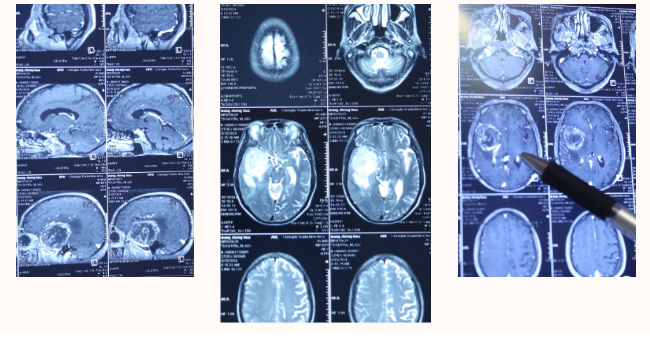

患者王某,今年70岁,以头痛头晕伴恶心10+天收入我院。从核磁共振影像可以明显看到,右侧颞叶有占位性病变,肿瘤面积较大,水肿也比较明显。从增强影像来看,肿瘤直径大小有9公分左右,相当大,周围水肿明显,脑组织受压移位,导致颅内压增高。因大脑中动脉及其分支血管从肿瘤中央穿过,导致手术有一定风险。

经多方了解后,在朋友的推荐下,患者慕名来到成都西南脑科医院找到了覃宗明主任。在覃主任的引荐下,北京天坛医院专家任天剑主任来到我院,两位专家一起对患者的病情及治疗方案等进行讨论。凭借多年的临床经验,结合患者影像结果判断为颅内胶质瘤,建议尽快实施手术切除。